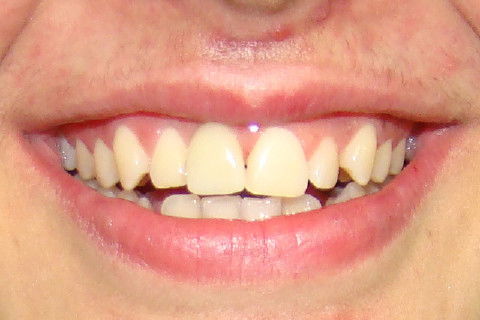

Retorno após 9 meses da colocação de coroa metalo-ceramica parafusada

Retorno após 9 meses da instalação de coroa metalo-ceramica parafusada

Paciente com implante feito em curso de atualização, chega ao consultório para reabertura e coroa metalo-ceramica unitária, com grande depressão gengival na vestibular do elemento 11. Feita a reabertura com concomitante enxerto de tecido conjuntivo para otimizar os tecidos moles, aguardamos 3 semanas para inicio das moldagens para a coroa temporária. Após colocação e ajustes da coroa temporária parafusada, aguardamos 3 meses para completa maturação dos tecidos e então fizemos nova moldagem, com personalização do transferente para moldeira aberta individual e fizemos coros metalo-cerâmica parafusada.